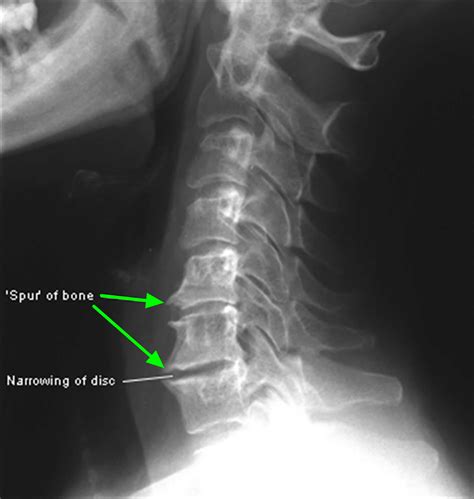

Medical Illustration Highlights Plantar Fasciitis, Heel Spur. Foot ...